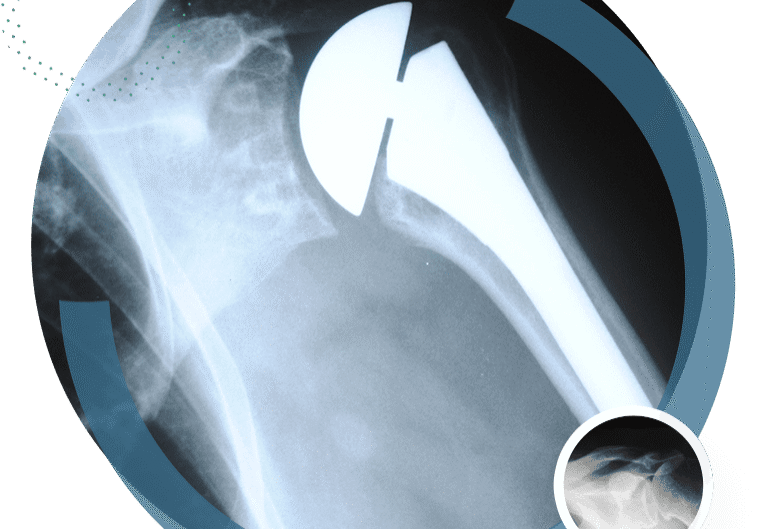

Shoulder Replacement Basics

I have performed nearly 2,000 shoulder replacements since I started practice in 2004. Initially, most...

Reverse Shoulder Replacement in San Diego

What to Expect During Recovery with Dr. Benjamin DuBois Shoulder pain from severe arthritis or...